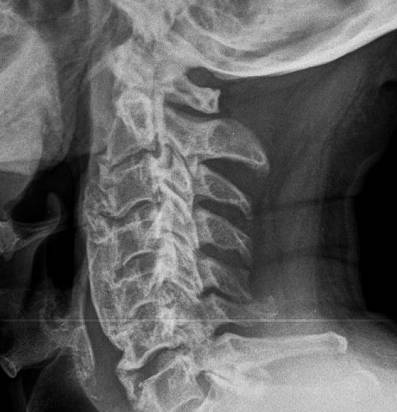

Несмотря на достижения современной медицины, выявить гиперостоз по клиническим признакам бывает довольно сложно. Наиболее информативным методом остается рентгенографическое исследование, а для точного определения локализации патологического процесса внутри костной структуры применяется томография. В некоторых случаях может потребоваться и радионуклидное исследование.

На рентгенограммах болезнь Форестье проявляется утолщением передней продольной связки, которая сливается с вентральными поверхностями тел позвонков, при этом высота межпозвонковых промежутков остается неизменной. В лабораторных анализах иногда наблюдается гипергликемия.

При проведении дифференциальной диагностики с другими деформирующими заболеваниями позвоночника важно учитывать отсутствие лабораторных признаков, проявлений воспалительной активности, сакроилеита, анкилоза межпозвонковых суставов и сужений межпозвонковых дисков.